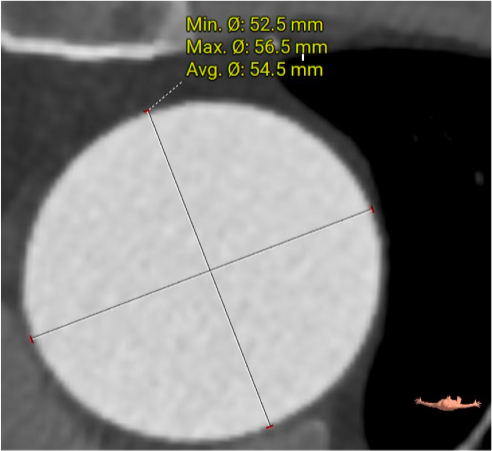

此患者解剖结构复杂:1)升主动脉明显增宽,平均直径达到54.5mm。

该结构需谨慎评估血管夹层和破裂风险,对瓣膜系统的通过性能要求极高。